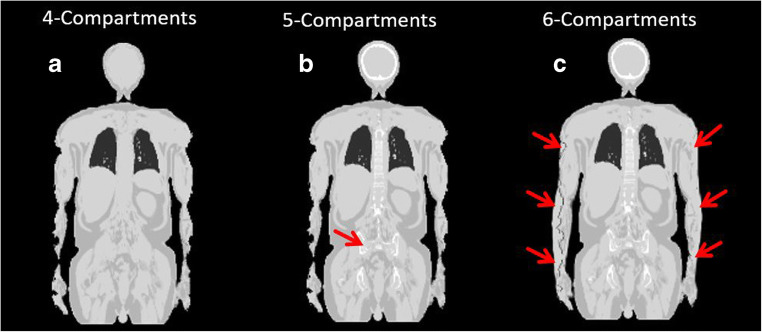

The segmentation from the CAIPIRINHA Dixon-VIBE sequence with added bone model and truncation correction with the HUGE method is referred to henceforth as the six-compartment μ-map (background air, lung, muscle, soft tissue, bone, HUGE) (Fig. 1) [12].

Fig. 1.

Segmentation from the improved CAIPIRINHA Dixon-VIBE sequence including bone model and MR-based truncation correction (HUGE). Example images of patient μ-maps: a four-compartment (background air, lung, muscle, soft tissue), b five-compartment with marked (red arrow) bone model (four-compartment plus bone), c six-compartment (four-compartment plus bone and HUGE truncation correction). The impact of HUGE truncation correction is marked with red arrows (c)

The HUGE technique proposed by Blumhagen et al. [10,19] is an MR-based technique for truncation correction of peripheral body regions and patient arms. In the present study, the most recent implementation of the HUGE technique was used, employing a moving table acquisition that provides up to 60 cm left-to-right seamless MRI coverage for the left and right arms of patients [11]. The truncation-corrected areas of the right and left sides of the body are then merged with the four-compartment reference μ-map, hence providing AC of the central and peripheral body regions as further compartment (Fig. 1).

Three different whole-body μ-maps were reconstructed for each patient: (1) the standard μ-map Dixon-based AC with 4-compartments serving as reference, (2) the 5-compartment μ-map, and (3) the 6-compartment μ-map (Fig. 1). All μ-maps and HUGE and MLAA raw data were inspected qualitatively for plausibility and artifacts. For each μ-map, it was visually examined how truncation correction with MLAA and HUGE performed in deriving the outer patient contours and to fill truncations along the arms with attenuation values.